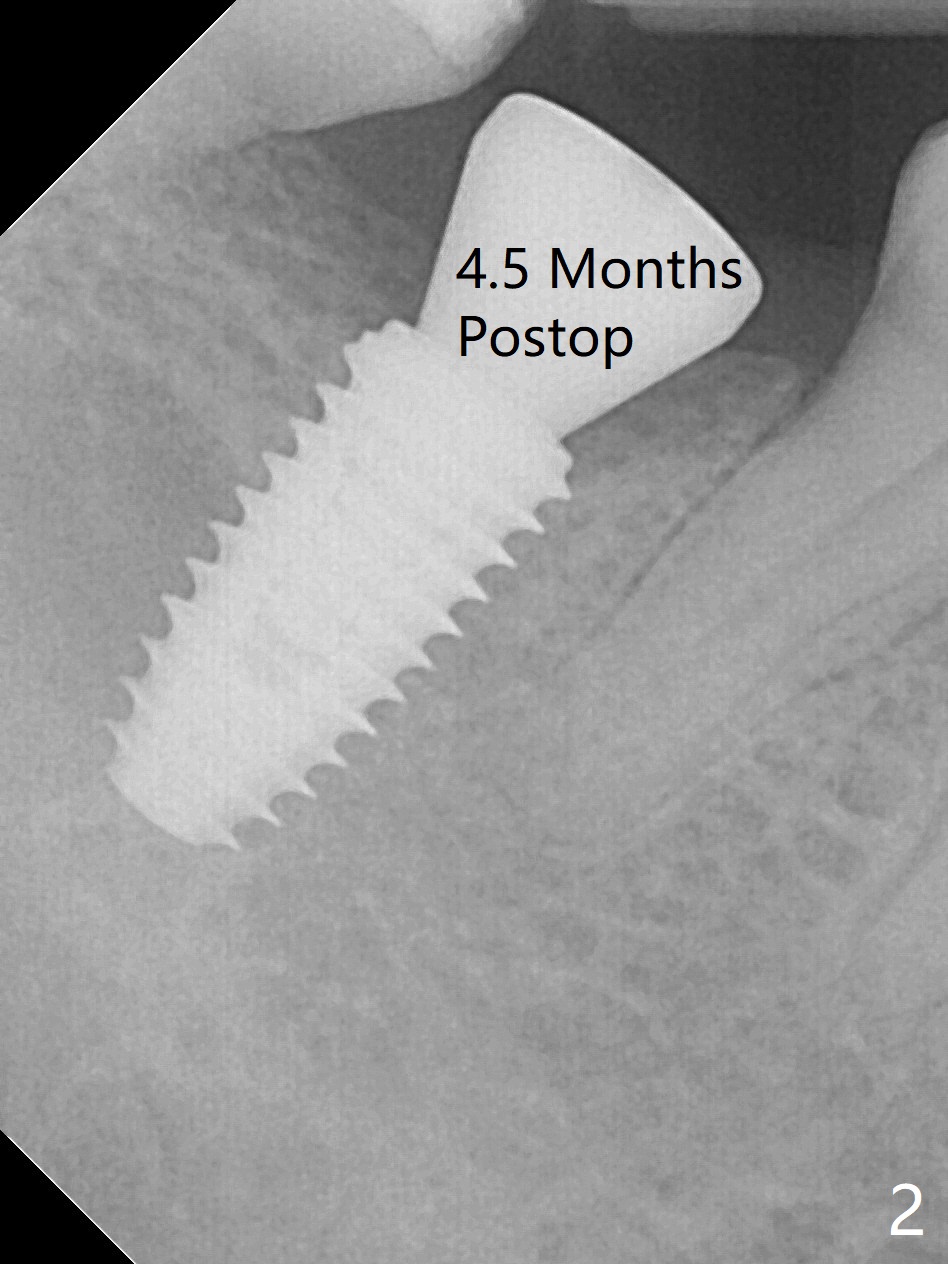

In fact 5x10 mm implant placement with guide requires using 5 mm cortical tap (Fig.1). When a 6x4 mm healing abutment is placed slightly supragingival, the clearance with the opposing supraerupted tooth is ~ 2 mm. It suggests that orthodontic intrusion is required for restoration. In fact the patient is incompliant with orthodontic mini-implant placement and retraction. When the implant at #31 is osteointegrated 4.5 months postop (Fig.2), it is used an anchor with an abutment and a provisional to intrude the opposing tooth. The final crown is cemented 10 months postop (Fig.3) with occlusal clearance (Fig.3' *). The contacts between #2 and 3 and between #31 and 32 are loose with papillary inflammation 5 months post cementation. It is planned to remove #31 crown/abutment for pick up impression/porcelain addition. Instead the crown is removed. After removing #32 MO composite with minor 2nd caries, new composite is placed (Fig.4 *) while the crown is reseated. When the crown is recemented, bitewing shows open margin (Fig.4), but the contact is wide and tight. After occlusal adjustment, occlusal contact at #31 and 32 mesial is heavier than that at #30. #3 crown is recommended. The occlusal table difference betweeen the upper 1st and 2nd molar is ~ 2 mmm preop (Fig.4'), whereas the difference is ~ .6 mm postop (in combination of occlusal equilibrium and intrusion of the upper 2nd molar (Fig.4)). It seems that orthodontic intrusion is not efficient in a male with bruxism. There is mild lingual (L) and distal bone loss 1.5 years post cementation (Fig.5) when CT is taken for #3 immediate implant. Lower Molar Immediate Implant, Armaments Xin Wei, DDS, PhD, MS 1st edition 07/12/2018, last revision 11/28/2020